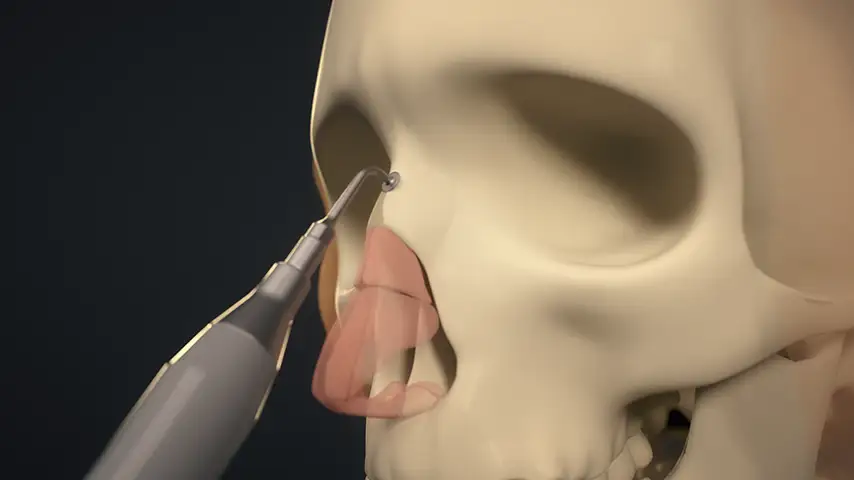

Clinical Applications of PIEZOSURGERY® technology

in Rhinoplasty

Hump takedown and dorsum modeling

Lateral osteotomy of nasal bone

Transverse osteotomy of nasal bone

Drilling of septum for suture fixation

Details

The finest and angled insert for insertion in limited space;

ideal for perforating nasal bones as well as ethmoid lamina splints.

Recommended insert:

Advantages over traditional tools

Reduced risk of damaging anatomically complex regions

Greater intraoperative control and bone management

Micrometric cut for minimal bone loss

Reduced heat generation to avoid bone necrosis